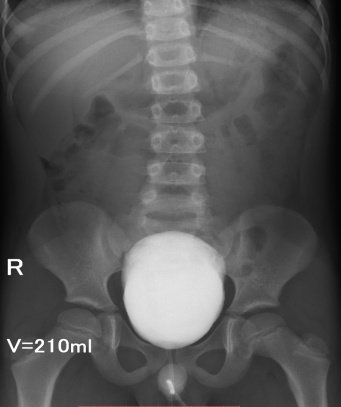

Медицинские изображения и примеры эксреторной цистографии